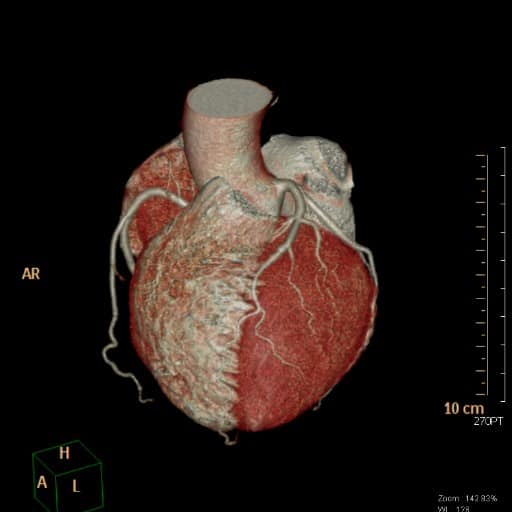

Mittels der Herz-CT können der Herzmuskel, die Herzkammern, die Herzklappen und vor allem die Herzkranzgefäße dargestellt werden.

Eine CT-Angiographie kann insbesondere sinnvoll sein bei Patienten ohne bekannte KHK mit unklarem Brustschmerz oder Atemnot, bei denen EKG-Untersuchungen, Echokardiographie und Bluttests keinen eindeutigen Hinweis auf eine Einengung der Herzkranzgefäße gezeigt haben. Die CT-A kann, auf der Basis unserer modernen CT-Technologie, die Herzkranzarterien hochaufgelöst und trotz schlagenden Herzens bewegungsfrei darstellen, so dass es uns Ärzten möglich ist, nicht nur Gefäßverschlüsse, sondern auch den Schweregrad einer Gefäßeinengung zu detektieren. Hieraus ergibt sich eine mögliche Aussage über die Notwendigkeit einer invasiven Herzkatheteruntersuchung bei einem Kardiologen zur weiteren Abklärung bzw. Behandlung des im CT erhobenen Befundes. Somit können durch die Herz-CT-Untersuchung unnötige invasive Herzkatheteruntersuchungen bei Patienten verringert werden.

Unsere neue CT-Gerätetechnik erreicht eine niedrige, individuell angepasste Strahlendosis mit einer hohen Bildqualität des bewegten Herzens durch die Kombination eines modernen Stellar-Detektors, einer erweiterten automatischen Strahlendosismodulation (FAST 3D-Camera, CareKv, CareDose) und einer hohen zeitlichen und räumlichen Auflösung (128 Schichten, Rotationszeit 0,33 Sekunden).Hierdurch ist es möglich, insbesondere die Herzkranzarterien nicht-invasiv in hoher Bildqualität darzustellen.

Die Auswertung der Herz-CT-Untersuchung erfolgt nach der Untersuchung durch die ärztlichen Kollegen mittels einer dezidierten Auswertesoftware mit Anfertigung selektiver Bilder der Herzkranzarterien und des gesamten Koronarbaumes. Durch die jahrelange Expertise von Dr. Andersen-van Loyen im Rahmen seiner vorherigen Tätigkeit als leitender Oberarzt mit Schwerpunkt in der radiologischen Herzbildgebung mit bereits mehreren tausenden befundeter Herz-CT-Untersuchungen kann unsere Praxis trotz der erst neu angeschafften Gerätetechnologie eine herausragende Fachkenntnis und Befundqualität gewährleisten.